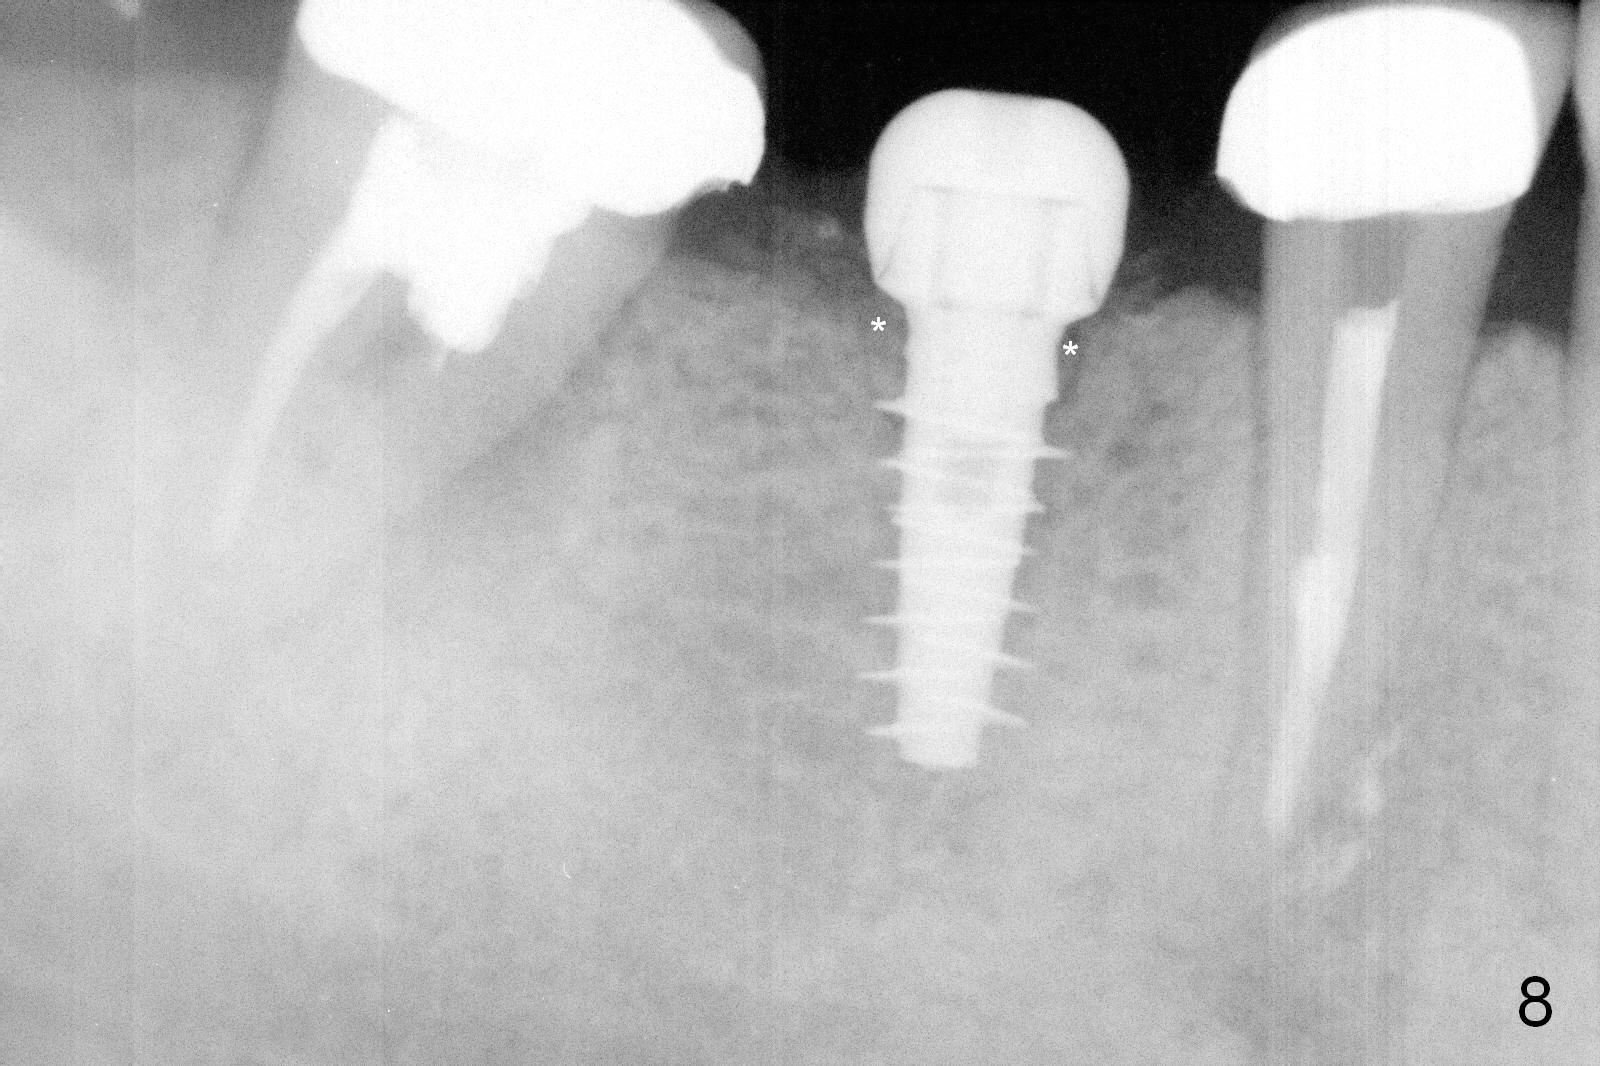

CBCT was taken (Fig.1,2 (P: pontic; S; submandibular fossa)) several months prior to #29 and 31 RCT and #31 porcelain chip (Fig.3). When the bridge is sectioned, the pointed ridge at #30 (Fig.1) is confirmed (Fig.4,5). After flattening the ridge until 6 mm buccolingually (Fig.6 arrowheads), osteotomy is initiated with 1.6 mm drill at 9 mm; there is 2.5 mm clearance from the superior border of the Inferior Alveolar Canal (red dashed line). A 4.5x9(1) mm Magicore is placed with 35 Ncm (insertion torque) after 4.3 mm Magic Drill; a 4.5 mm healing abutment (Fig.7 H). An error occurs because of using 1 mm cuff of the Magicore. Ideally 3 or 4 mm cuff should have been used because of reduction of the ridge by ~ 3 mm (Fig.2). The result of the error is failure of placing the implant at the desirable depth (<9 mm). The coronal threads are exposed and have to be covered by bone graft (autogenous bone and allograft (.5-1.5 mm) (Fig.8 *), followed by collagen dressing. Extra suturing is done to securely close the wound (Fig.9), followed by periodontal dressing (data not shown).

Splinted provisional is fabricated #30 and 31 one month postop. The patient returns for final restoration (single units) nearly 4 months postop (Fig.11). Since the margin is subgingival, a screw type crown is fabricated for #30 (Fig.12). The buccal gingiva looks convex after healing cap removal (Fig.13, as compared to Fig.4 (concave)). PA is taken immediately post tightening and cementation (Fig.14, 5 months postop). It appears that new bone has grown between the most coronal threads (arrows). The bone density immediately around the implant appears to increase 1.5 years post cementation (Fig.15,16). She returns because of failure of 18-20 bridge (implants will be placed at 18/19). The implant at #30 is in fact not placed deep enough; the coronal threads seem to be exposed, although there is no periimplantitis (Fig.17 CT). The tooth #31 is symptomatic; the mesial canal is missing (Fig.18 M, <). The gingiva around the crowns at #30 and 31 remains healthy 2 years 4 months post cementation (Fig.19). Metal exposure of the crown at #31 is intentional. Occlusal reduction is done to alleviate periapical re-infection (Fig.18).